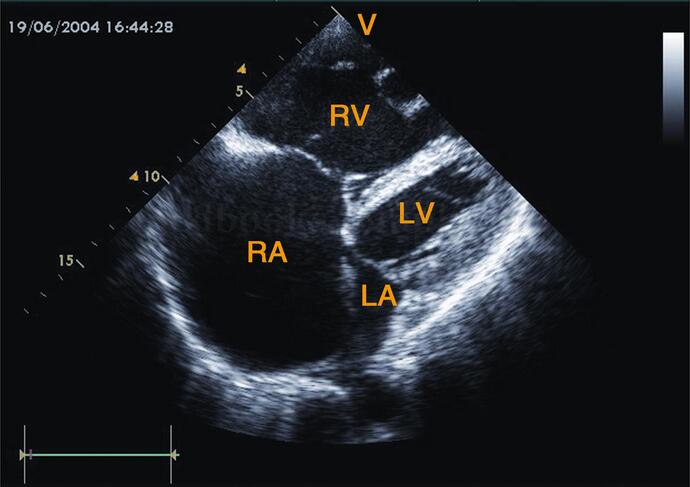

(1)四个房室腔均明显增大,以左室、左房为著。侵犯右心的心肌病表现右心扩大为主(图2‐1‐184)。

图2‐1‐184 侵犯右心的心肌病,右房、右室明显扩大